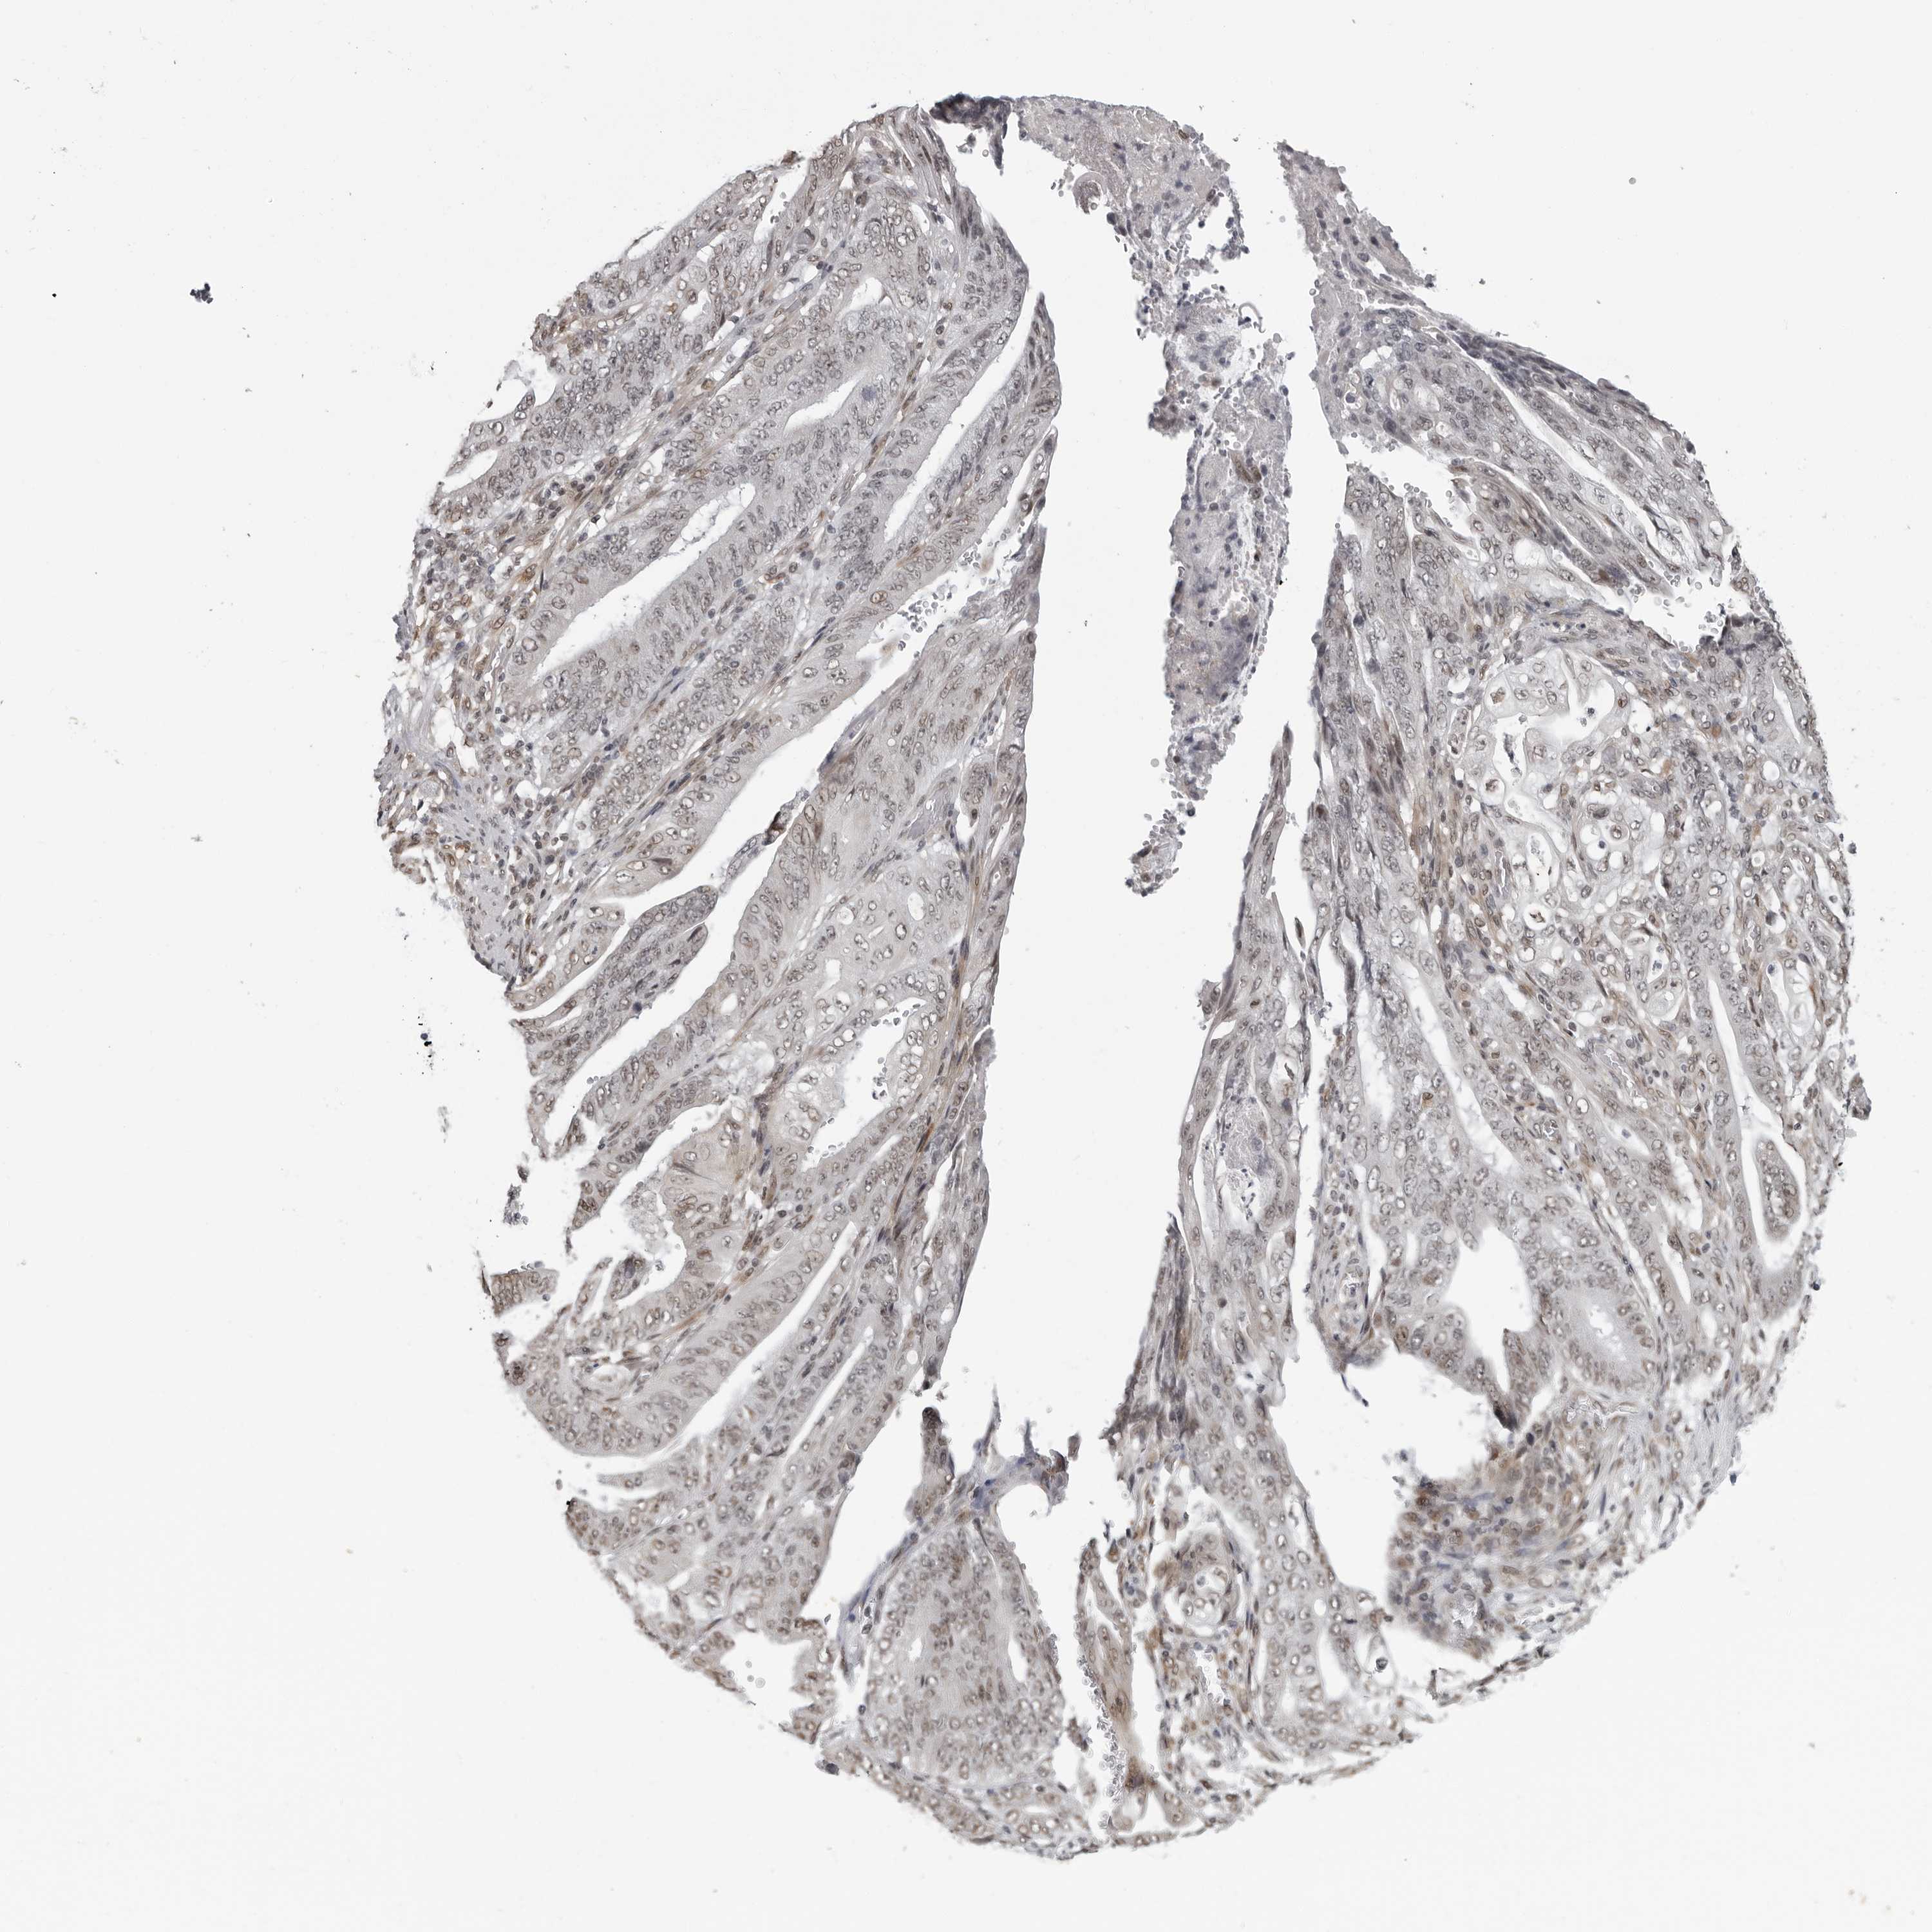

STOMACH CANCER - Protein expressioni

A mouse-over function shows sample information and annotation data. Click on an image to view it in a full screen mode. Samples can be filtered based on level of antibody staining by selecting one or several of the following categories: high, medium, low and not detected. The assay and annotation is described here.

Note that samples used for immunohistochemistry by the Human Protein Atlas do not correspond to samples in the TCGA dataset.

Antibody stainingi

Antibody staining in the annotated cell types in the current human tissue is reported as not detected, low, medium, or high, based on conventional immunohistochemistry profiling in selected tissues. This score is based on the combination of the staining intensity and fraction of stained cells.

Each image is clickable and will lead to virtual microscopy that enables deeper exploration of all samples and also displays staining intensity scores, fraction scores and subcellular localization as well as patient and tissue information for each sample.

Antibody HPA028289

Antibody CAB010296

Staining

High

Medium

Low

Not detected

Intensity

Strong

Moderate

Weak

Negative

Quantity

>75%

75%-25%

<25%

None

Location

Nuclear

Cytoplasmic/membranous

Cytoplasmic/membranous,nuclear

Adenocarcinoma, NOS

Adenocarcinoma, High grade